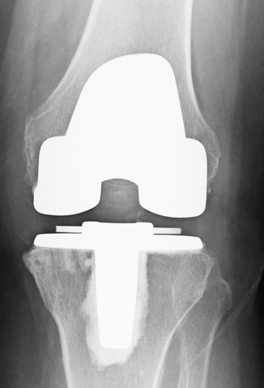

(常規(guī)全膝關(guān)節(jié)置換術(shù)后X光片)

微創(chuàng)膝單髁置換術(shù)與全膝關(guān)節(jié)置換術(shù)相比,優(yōu)勢(shì)十分明顯。微創(chuàng)膝單髁置換術(shù)具有手術(shù)切口小,損傷小,出血少,無(wú)需輸血;術(shù)后疼痛少,術(shù)后第2天即能下地行走,術(shù)后3天可以出院。2017年6月以來(lái),柳州市人民醫(yī)院關(guān)節(jié)骨病運(yùn)動(dòng)醫(yī)學(xué)科以彭偉秋博士為首的團(tuán)隊(duì),積極學(xué)習(xí)和引進(jìn)新技術(shù),在柳州市率先成功開展了膝關(guān)節(jié)單髁置換手術(shù)。柳州380萬(wàn)人口中20%是60歲以上老人,76萬(wàn)老人中約有50萬(wàn)老人患有老年性膝骨性關(guān)節(jié)炎,其中3%是處于晚期。由于晚期老年性膝骨性關(guān)節(jié)炎致殘,病人無(wú)法生活自理,給家庭和社會(huì)帶來(lái)了較重的負(fù)擔(dān)。我院開展的微創(chuàng)膝單髁置換術(shù)實(shí)現(xiàn)了對(duì)晚期膝骨性關(guān)節(jié)炎的精準(zhǔn)優(yōu)化治療,具有康復(fù)快,療效優(yōu),病人樂(lè)意接受等特點(diǎn),為保障老百姓的健康提供了新方案。